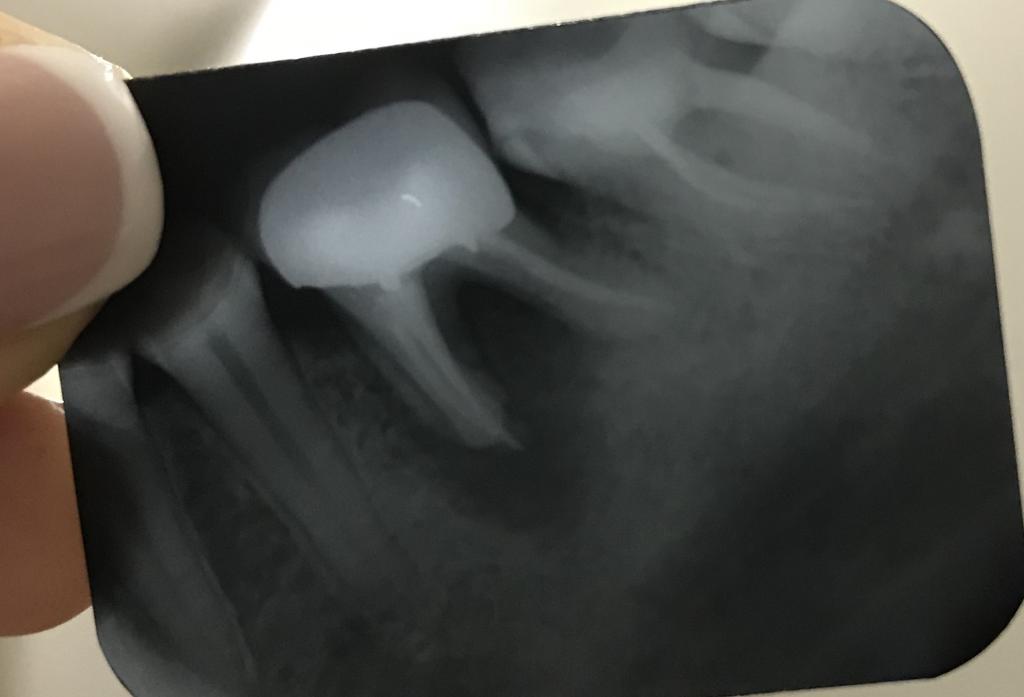

Проконсультируйте,пожалуйста. 2 года стоит коронка на нижней левой 6-ке. Периодически болела десна под коронкой и при накусывании сам зуб. Ходила к своему врачу,она говорила,что это из за воспаления десен и колола мне лекарства. Вроде как проходило,но последние пол года начало тянуть и болеть часто + появилась припухлость внутри на десне со стороны щеки.

По снимку сказали, что кистообразная гранулема. Ходила на консультацию к разным врачам,предложили такие варианты:

1) не снимая коронку вырезать корень с кистой сбоку челюсти, заполнить костной тканью и зашить.

2) снять коронку и попробовать полечить, но это без гарантии сохранения зуба

3) удалить зуб (тк сказал,что нет смысла возиться уже с ним,слишком глубоко повреждена десна и потом может опять появиться тоже самое) и ставить потом имплант.

Есть ли тут вариант не удалять зуб или все таки он безнадежен?

К сожалению на удаление,лично моё мнение.

4) после снятия коронки провести сепарацию корней, удалить медиальный корень и вычистить все грануляции; если дистальный корень не имеет выраженной подвижности, можно попробовать его сохранить. После ревизии и восстановления корня, объединить его с 7-кой в 2 коронки (т.к. 7-й неживой, и коронка у него в перспективе). Разумеется, коронками накрыть после полного заживления.